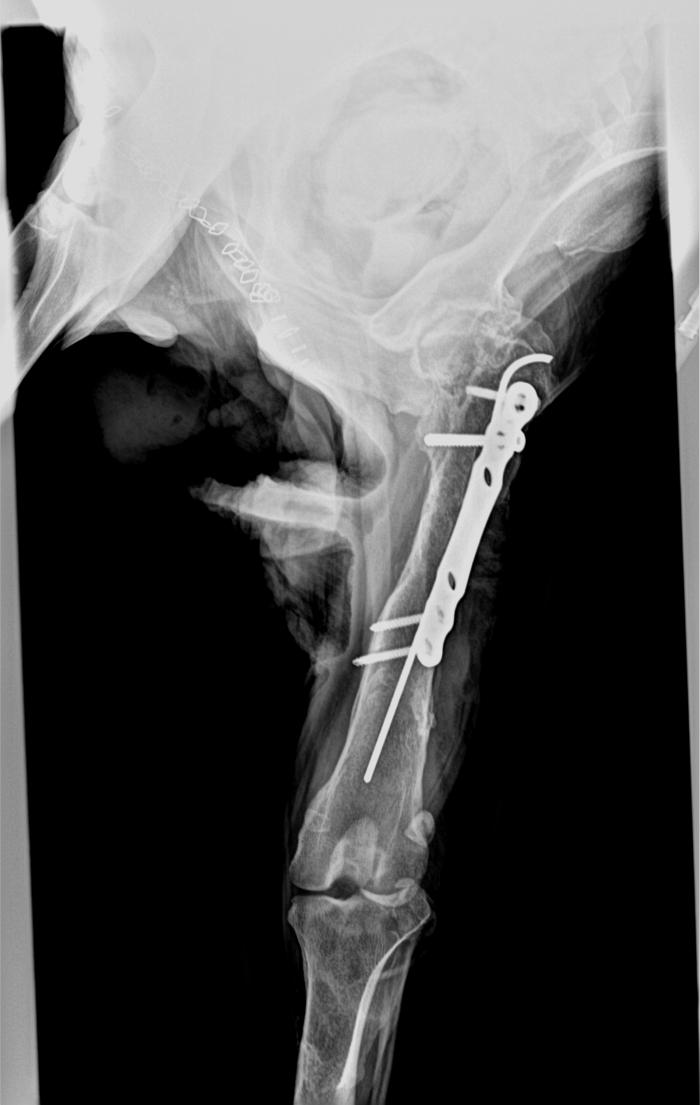

Las analíticas denotan una leve leucotiosis neutrofílica sin otras alteraciones relevantes. Las radiografías denotan una fractura de fémur antigua y reducida con placa de bloqueo y clavo intramedular, aparentemente consolidada (Figura2).